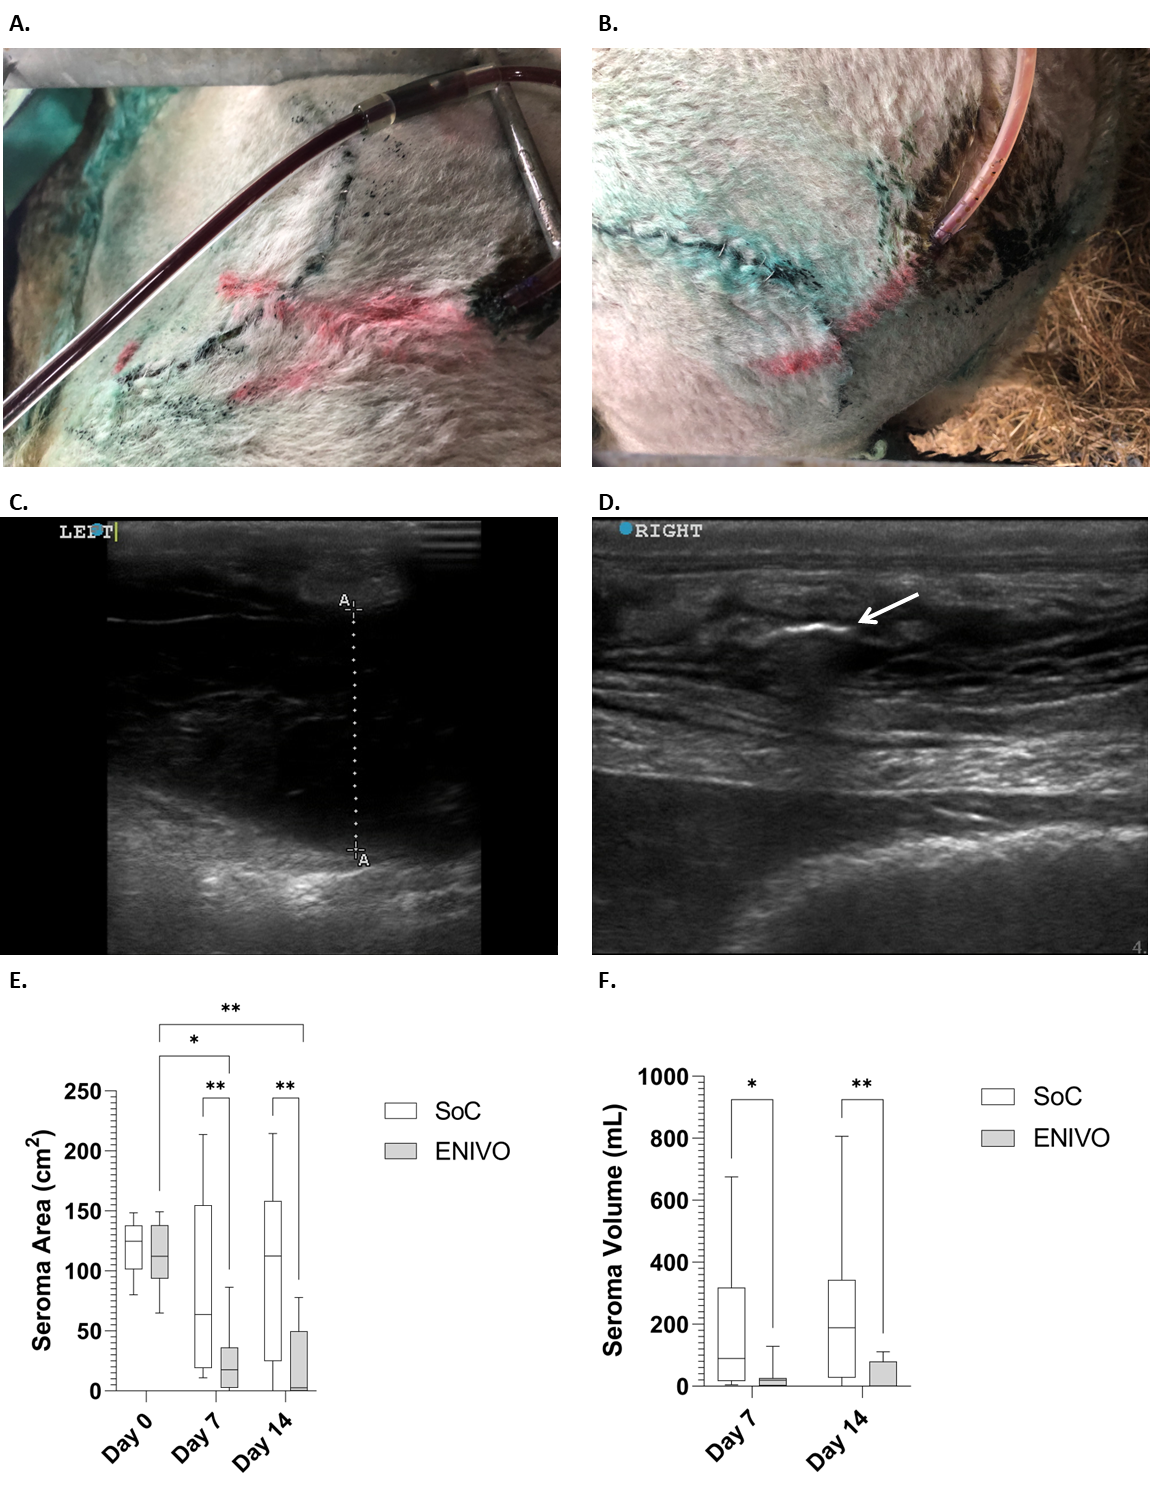

Fibrous material accumulated in the SoC drains from postoperative day ~1 to 2, whereas the extent of fibrinous material in the ENIVO drain catheter was less apparent visually (Figure 4a and 4b). Seromas were clinically observable by postoperative days 3 to 7 and were clearly visible via ultrasound (Figure 4c). Seroma area and seroma volume as determined from ultrasound are presented in Table 4 and Figure 4. By day 7, defects treated with SoC had a median seroma area and volume of 63.6 (IQR 19.1-154.7) cm2 and 89.9 (IQR 17.3-318.3) mL, respectively (Table 4). In comparison ENIVO treatment led to a significantly reduced median seroma area [17.7 (IQR 2.7-36.2) cm2], and seroma volume [19.6 (IQR 2.4-26.3) mL], compared with SoC treatment. At day 14 the differences were more pronounced with ENIVO-treated defects having significantly reduced median seroma area and seroma volume [2.5 (IQR 0.0-49.6) cm2 and 1.3 (IQR 0.0-79.5) mL] compared with that of the SoC group. Seroma area of ENIVO-treated defects at day 7 and day 14 were statistically smaller relative to the day 0 total defect area (Dtotal). The seroma areas at day 7 and day 14 were also expressed as a percentage change relative to the total defect areas (Dtotal;Table 4). Percentage seroma area change at day 7 and day 14 for the SoC-treated defects were 79.0% (IQR 15.5%-142.0%) and 98.0% (IQR 19.5%-128.5%), respectively, with 4 of the 10 defects increasing in area relative to the measured area at day 0 (Dtotal). In contrast, ENIVO-treated defects at days 7 and 14 were 13.0% (IQR 2.5%-42.5%) and 2.0% (IQR 0.0%-55.0%) of the original total defect area (Dtotal), respectively. The cumulative drain fluid output was determined over the course of the study (Table 5 and Figure 5). At all timepoints ENIVO-treated defects resulted in an increase in the cumulative drain fluid volume output (Figure 5a). At day 14 the mean cumulative volume collected by the ENIVO devices was approximately triple that of the SoC devices, 178.4 ± 23.2 mL versus 64.1 ± 14.8, P = .0026 (Figure 5b). In both treatment groups the majority of the fluid output was collected in the first 3 days (Figure 5a). At day 14 treatment in both groups was ceased. Following the postoperative day 14 ultrasound assessment, ENIVO and SoC drains were removed and the maximum force required to remove each drain measured. The mean maximum drain pull force required to remove an ENIVO drain catheter was statistically higher than that for the SoC drains, 11.68 ± 2.11 N and 3.66 ± 1.12 N, respectively (Table 4 and Figure 6a). Drain migration was assessed at postoperative days 7 and 14 and scored according to Table 1. At days 7 and 14, 8 of 9 (89%) ENIVO drains were judged as having no migration from the original position within the defect (Figure 6b). In contrast, SoC drains were relatively mobile, with over half the drains being assessed as having migrated from their original position by postoperative day 7.

The ENIVO system has been designed to address shortcomings with existing technologies for dead space management and seroma prophylaxis. Treatment with the ENIVO system resulted in reduced seroma area and seroma volume at days 7 and 14 (Figure 4) and over the course of 14 days drew more fluid from the defect versus SoC (Figure 5a). At the 28-day euthanization, 9 of 9 (100%) defect treatments were judged clinically successful with use of the ENIVO system versus only 6 out of 10 (60%) for the SoC treatment. The absence of any residual seroma correlated to strength and tenacity of the tissue apposition, with ENIVO-treated sites having a statistically higher tissue apposition score versus SoC-treated sites.